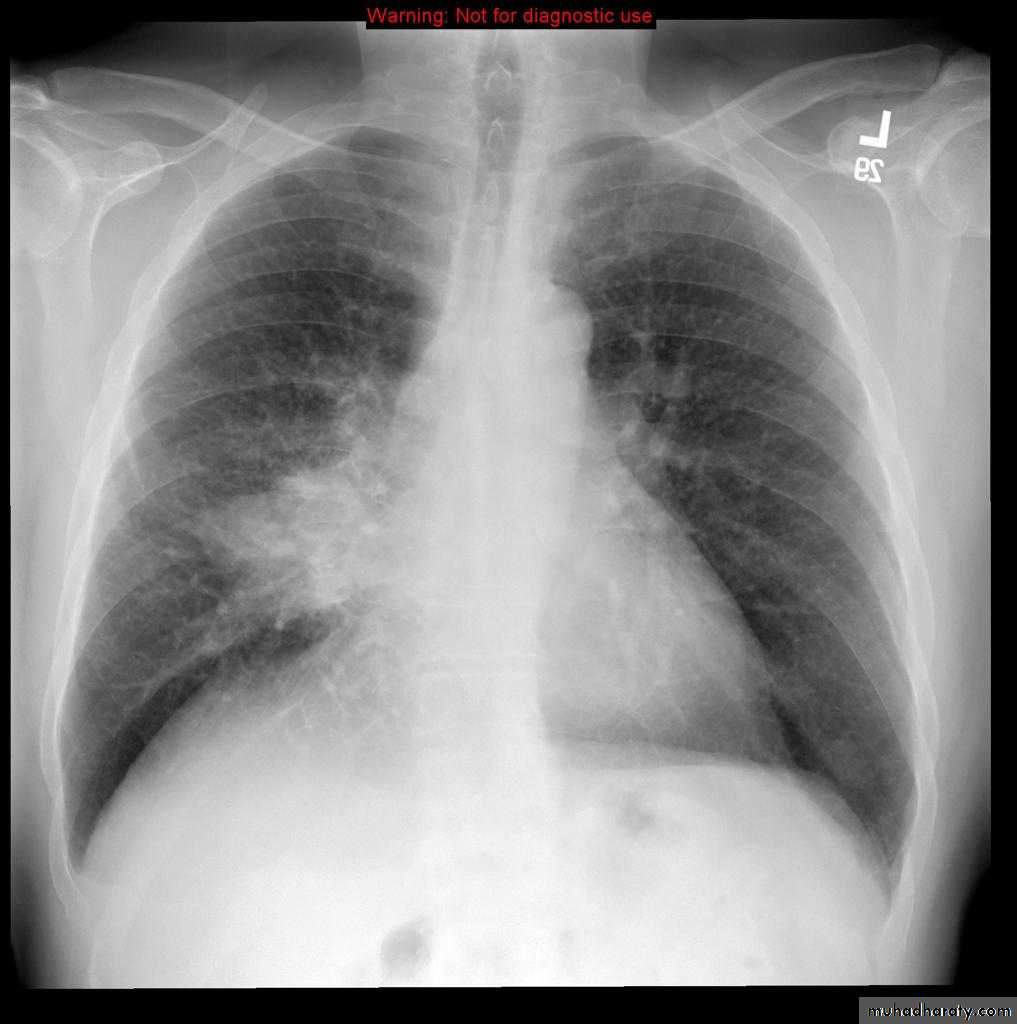

Pulmonary emphysema

Pulmonary emphysema is defined as the "abnormal permanent enlargement of the airspaces distal to the terminal bronchioles accompanied by destruction of the alveolar wall and without obvious fibrosis". Emphysema is one of the entities grouped together as chronic obstructive pulmonary diseaseRadiographic features

Plain film

Except in the case of very advanced disease with bulla formation, chest radiography does not image emphysema directly, but rather infers the diagnosis due to associated features :

hyperinflation:

1.flattened hemidiaphragm(s): most reliable sign

2.ncreased and usually irregular radiolucency of the lungs

3.increased retrosternal airspace

4.increased antero-posterior diameter of chest

5.widely spaced ribs

6.sternal bowing

7.tenting of the diaphragm

8.saber-sheath trachea

9.vascular changes paucity of blood vessels ( absent pulmonary markings in outer 1/3 of the lung fields )

10 .pulmonary arterial hypertension

pruning of peripheral vessels

increased calibre of central arteries

right ventricular enlargement

Emphyzema